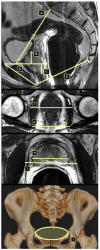

Methods: Preoperative MRI was performed in 482 Caucasian and 103 African American (AA) men undergoing RP without previous treatment from July 2003 to January 2005 and November 2001 to June 2007, respectively. We measured bony and soft tissue dimensions on magnetic resonance imaging (MRI) to evaluate the pelvic inlet, midplane, prostate size, and apical depth. Analysis of covariance was performed to determine the effect of ethnicity on the midpelvic area (MPA). We performed multivariate logistic regression analysis for prediction of overall and site-specific PSM.

Results: AA men had a significantly steeper symphysis pubis angle (median, 43.1 vs. 41.3°, respectively, P = .001) and smaller MPA (median, 78.5 vs. 83.9 cm(2), respectively, P = .004). Ethnicity and BMI were found to have a significant effect on MPA. Apical depth of the prostate was identified as a significant independent predictor of apical PSM, with a more pronounced effect in AA men. Pelvimetric measures were not a significant predictor of other sites of PSM.

Conclusions: AA men have a significantly smaller MPA and steeper symphysis angle. The adverse impact of a deep pelvis, as measured by the apical prostatic depth on apical PSM was found to be greater in AA men. Evaluation of pelvic dimensions and prostate parameters in preoperative MRI may add to our understanding of their impact on surgical outcomes.